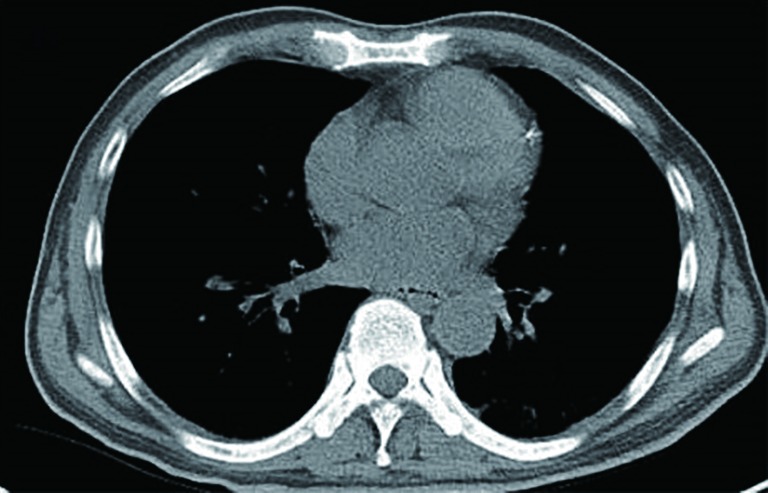

The pleural fluid was light yellow and highly cellular, in which 75% was mononuclear cells. Results from the analyses of the right side pleural fluid indicate an exudative type according to the Light criteria (3), which contained total protein 56.2 g/L, albumin 18.3 g/L, globulin 37.9 g/L, A/G 0.5, lactic dehydrogenase (LDH) 142.0 U/L, a-hydroxybutyrate dehydrogenase (aHBDH) 172.7 U/L, adenosine deaminase (ADA) 62.4 U/L. No acid-resistant bacilli were found. Computed tomography (CT) image of the chest (axial view) indicated bilateral sided pleural effusion and distinctive pleural nodular-like thickening as shown in Figure 1. The posteroanterior skull radiographs demonstrated low craniofacial bones density, and saccate transparent area could be seen without any signs of fractures. The posteroanterior view of pelvis was normal. The single photon emission computed tomography (SP-ECT) scan indicated metabolic disturbance of skull bones and elevated metabolism condition of the middle of left humerus.

Figure 1.

Computed tomography (CT) of the thorax before the chemotherapy: initial image showed bilateral pleural effusions (red arrows) and distinctive nodular-like thickening of bilateral pleural with apparent enhancement (black arrows).